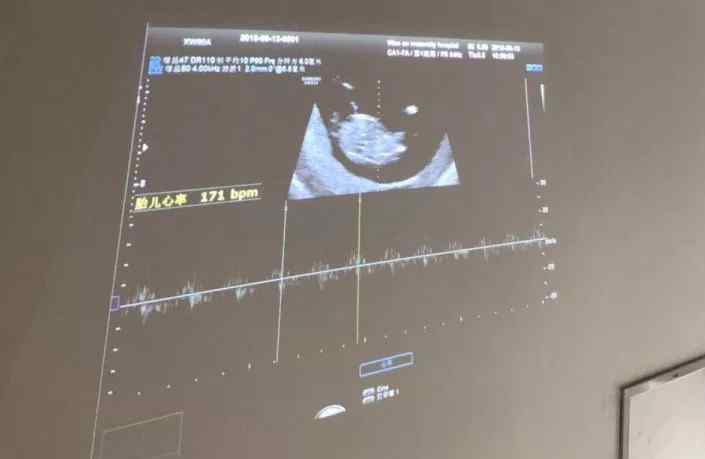

来太和和和美妇产医院做5D彩超

五维(5D)彩色多普勒超声具有极高的清晰度和分辨率,可以360度显示胎儿宫内发育情况。与众所周知的四维彩色多普勒超声相比,它具有更高的清晰度和更全面的诊断范围。可以从更多的方向和角度观察宫内胎儿的生长发育。在检查的同时,包的父母也能看到他聪明的外表和像看电影一样的一举一动。

太和和合美妇产医院5D彩超室实行人性化的内外设计。在保证安全健康的情况下,允许并鼓励待产父亲陪同孕妇到5D彩色超声室检查,孕妇躺在床上检查,通过显示屏可以观察到婴儿在腹部的运动。

此外,在彩色超声工作室外设置现场观察屏,让全家人分享胎儿实时动态图像,每个家庭分享人生的第一个感动瞬间。